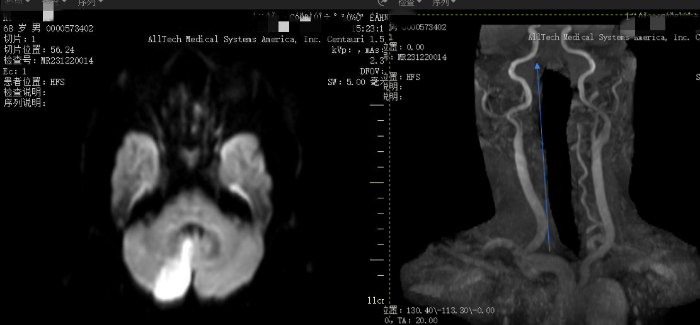

張某,男性,今年(nián)68歲,因頭暈、行走不穩半月爲主訴來(lái)院就(jiù)診。神經内科(kē)一病區醫生(shēng)李濤完善顱腦DWI檢查(核磁共振檢查擴散加權成像)序列顯示:右側小腦半球急性腦梗塞;頭顱MRA+頸部MRA(磁共振動脈血管成像)顯示:雙側大(dà)腦後動脈、基底動脈及左側椎動脈V5段顯影(yǐng)淺淡,右側椎動脈未見(jiàn)明顯顯示,左側椎動脈V1段起始段局限性狹窄。